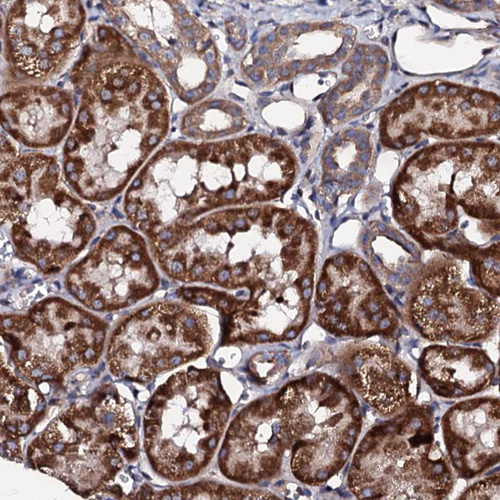

Immunohistochemical staining of human testis shows strong granular cytoplasmic positivity in cells in seminiferous ducts.